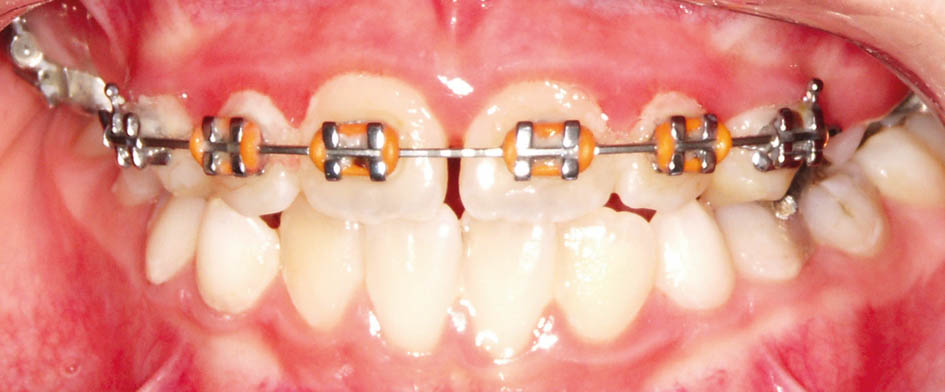

همانطور که ذکر گردید برای کراس خلفی یک پیچ RPE (شکل 41-5) بههمراه اسپیلینت پائین و برای کراس قدامی دندانها، چند براکت و یک اسپیلینت آکریلی پائین بسازید (اسپیلینت آکریلی پائین در هر دو درمان فوق مشترک است).

شکل 41-5: ساخت RPE برای درمان کراس بایت خلفی و چسباندن چند براکت برای پروترود کردن قدامیها جهت درمان کراس بایت قدامی، البته در فک پائین باید یک اسپیلینت متحرک آکریلی داشته باشد.